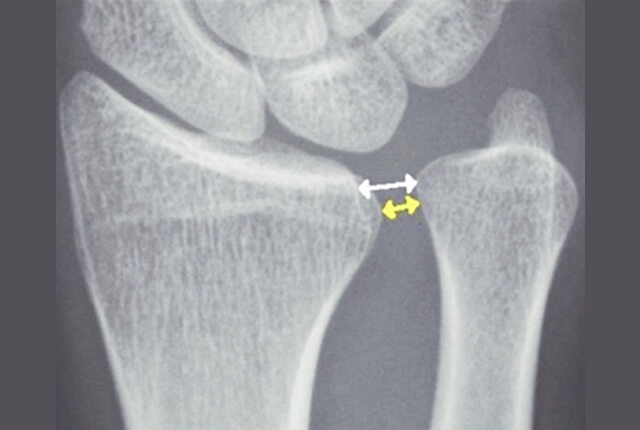

• 単純X線でDRUJの開大

単純X線でDRUJの開大